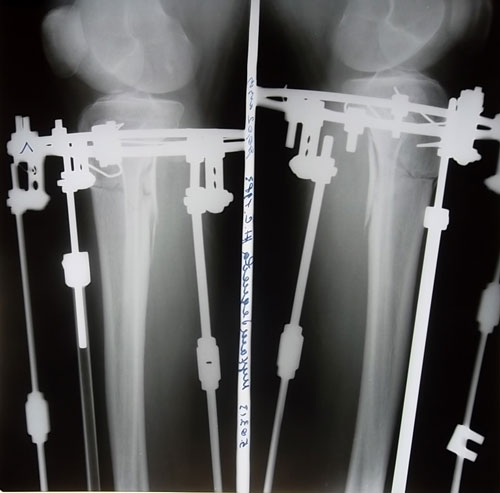

Сегодня день прошел не заметно. Приходил Константин Николаевич. Я ходила на рентген. Приходила секретарь делала снимки ножек. Много ходила что левая нога каждый раз затекала. Приходилось периодически ложиться и поднимать ноги. А так хотелось больше ходить и ходить. Тем более что тут новенькие охото поболтать с ними. Сегодня приехала еще одна девочка на ОП. Очень рада за них они все по акции делают. Повезло им. Я сегодня впервые ходила на кастылях и спускалась на них по ступенькам. Такая довольная. И сегодня я очень устала.